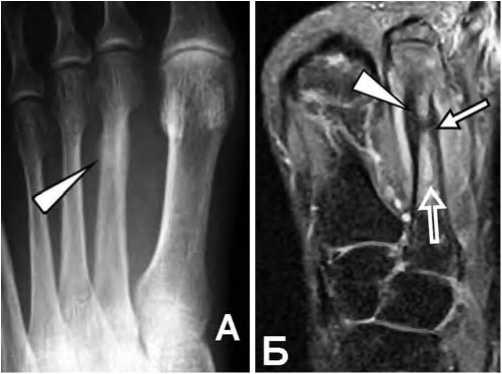

Рис. 7. Маршевый Перелом.

А: Рентгенограмма левой стопы в прямой проекции. Участок неравномерного утолщения диафиза второй плюсневой кости(стрелка), линия перелома четко не прослеживается.

Б: FS PD FSE. томограмма в косой коронарной проекции показывает повышение сигнала от костного мозга в области диафиза второй плюсневой кости (нижняя стрелка), гипоинтенсивную линию перелома (обычная стрелка) и периостальную реакцию (треугольная стрелка).